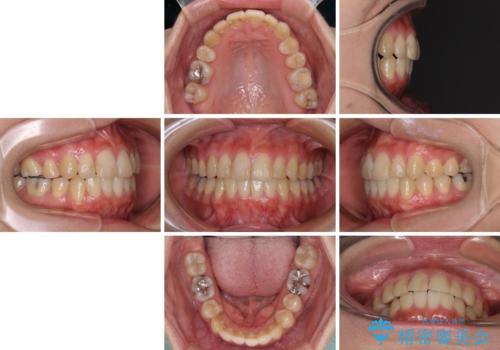

右側のみ上下小臼歯を抜歯したため、上下の正中が右にずれてしまう可能性があります。

また、元々右側は上下が咬み合っていないため、矯正をしても咬み合わないことも考えられました。

治療期間はかかりましたが、正中も合い、綺麗な仕上がりとなりました。